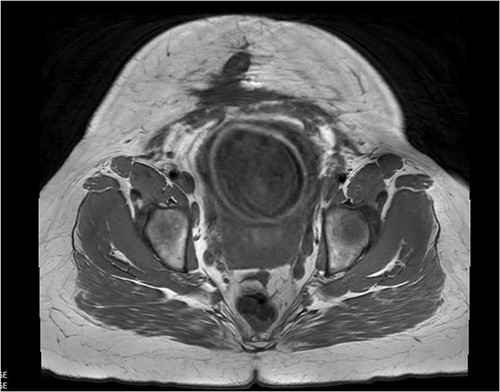

In the first trimester of her third pregnancy, she developed purulent drainage with bleeding and pain at the inferior portion of the vertical scar (Fig. 1). This drainage, in addition to abdominal pain, caused her to seek care. She was admitted for IV antibiotics and discharged home to complete a course of oral antibiotics. She had ongoing interdisciplinary care throughout her pregnancy including her local obstetrician, a consulting MFM specialist, and general surgery (GS). She intermittently received antibiotics for worsening symptoms. An MRI was obtained (Fig. 2) in the third trimester to further characterize the abdominal wall. No abscesses were visualized.